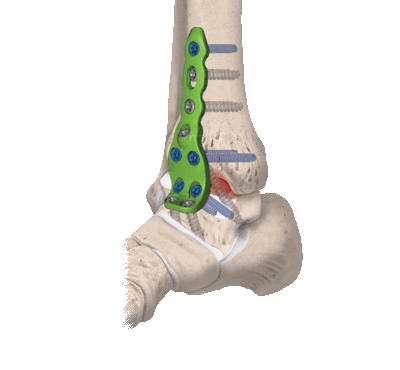

Открытая репозиция с внутренней фиксацией

Метод применяют для лечения сложных переломов, когда невозможна ручная репозиция отломков и удержание их в нужной позиции с помощью гипса. Чтобы сопоставить костные фрагменты и надежно зафиксировать их, используют погружные элементы и конструкции:

- болты-стяжки;

- винты;

- болты с клеммами-накладками;

- спицы Киршнера;

- болты с гибкой тягой;

- лавсановые ленты и прочее.

Открытая репозиция обеспечивает одномоментное точное сопоставление отломков и их надежную фиксацию. После операции нередко сохраняется ранняя опороспособность конечности, что позволяет нагружать ее вскоре после операции. И тем не менее многие специалисты уверены, что ни один из методов открытой репозиции не может обеспечить полной неподвижности костных фрагментов. Поэтому после операции пациентам требуется дополнительная гипсовая иммобилизация.